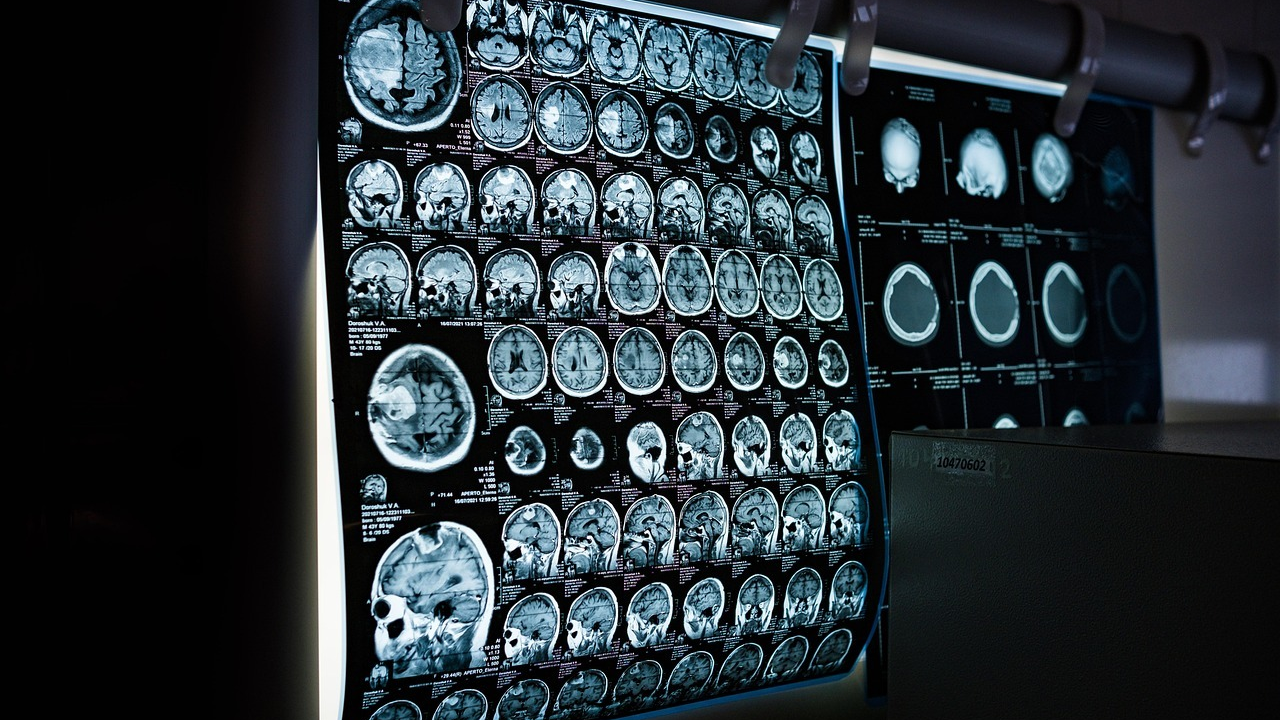

Osobe s multiplom sklerozom u Hrvatskoj od ovoga mjeseca imaju mogućnost liječenja sa svom dostupnom terapijom odmah nakon postavljanja dijagnoze, što znači da će manji broj oboljelih razviti invaliditet, istaknuli su u ponedjeljak predstavnici neurološke struke i pacijenata.

"Zbog restrikcija hrvatski su bolesnici imali znatno veći stupanj neurološke onesposobljenosti u odnosu na slovenske pacijente kojima su svi lijekovi bili jednako dostupni. No, i Hrvatska sada ima neograničen pristup terapijama za multiplu sklerozu", ustvrdio je na konferenciji za novinare neurolog Mario Habek s KBC-a Zagreb.

Na konferenciji su predstavljene promjene za oboljele od MS-a nakon stupanja na snagu nove liste lijekova HZZO-a, 10. veljače, a kojom se ukidaju diskriminirajući kriteriji da bi oboljela osoba mogla dobiti najučinkovitiju terapiju.

Prema zadnjim podacima HZJZ-a iz rujna 2024., u Hrvatskoj je 8518 osoba s MS-om, a broj oboljelih je u porastu iz godine u godinu.

"Ako ne liječimo bolesnika, nakon 20 godina više od 80 posto će ih imati nepovratnu neurološku invalidnost. Kada imamo samo umjereno učinkovitu terapiju, taj postotak pada na oko 30 posto, a s visokoučinkovitom terapijom postaje zanemariv", rekao je.